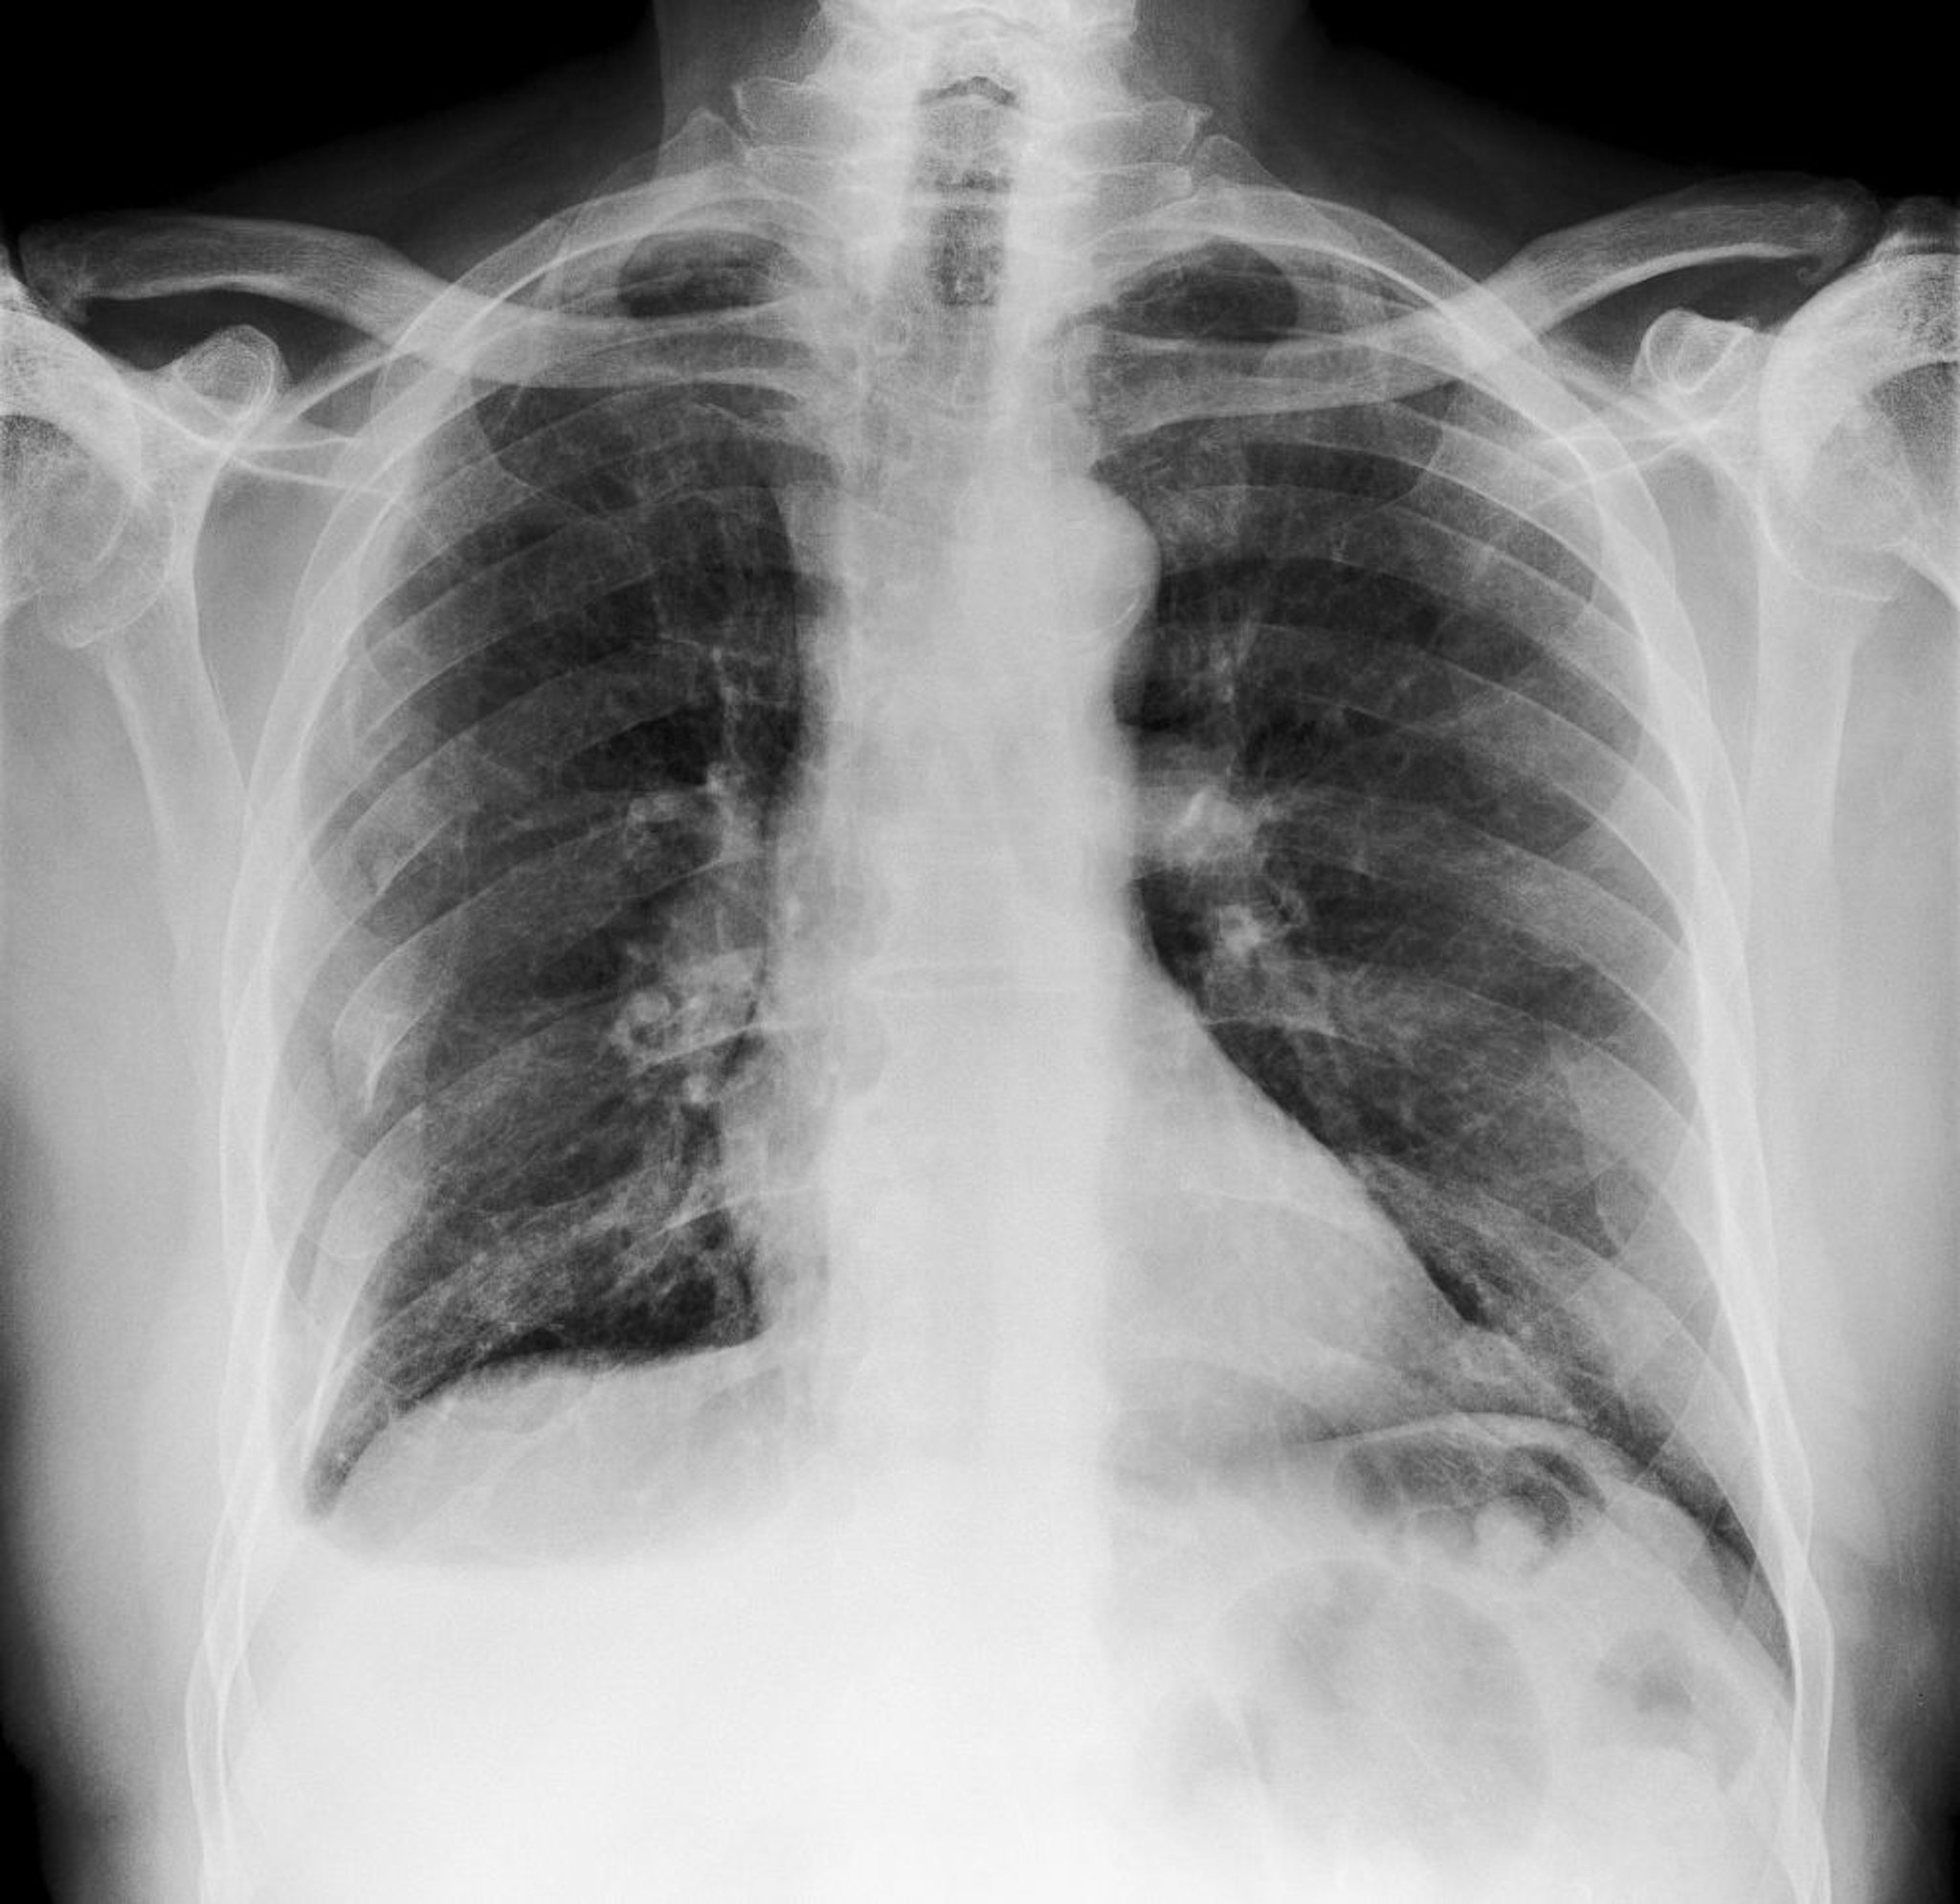

Этот рентгеновский снимок грудной клетки показывает множественные переломы ребер справа (вид слева).